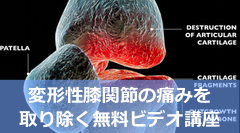

膝伸展・荷重痛について

考えていこうと思います。

膝の構造を考えると、

この筋は膝の痛みとの

関連性が高い例が多いです。

膝組織の構造から痛みを考えると

評価の前段階でどのポイントを

評価するか絞り込みやすくなります。

その膝伸展・荷重痛への

治療アイデアをご紹介です。